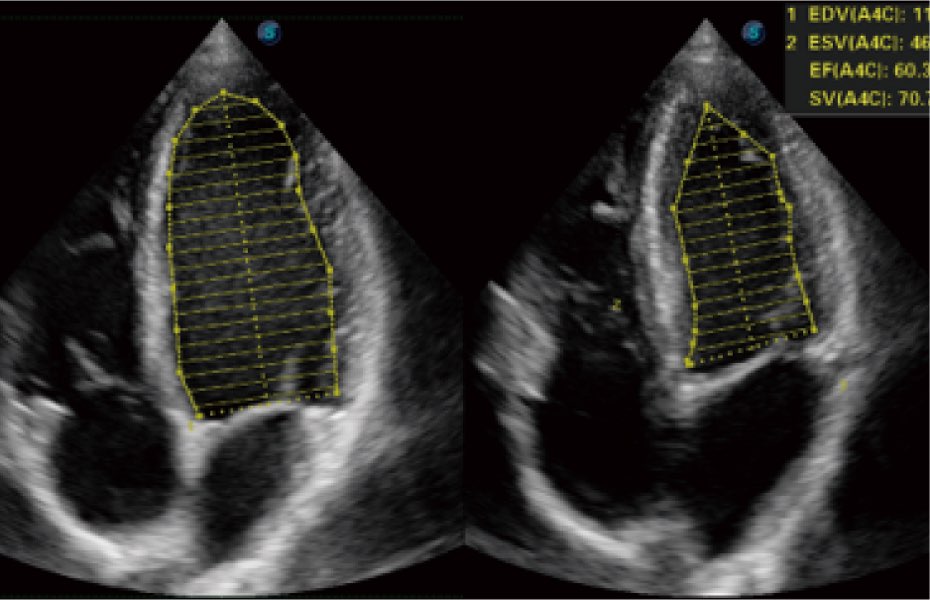

Przy pracach nad aparatem ProPet 60 uwzględniono najważniejsze preferencje i potrzeby weterynarzy, oferując finalnie przystępne cenowo i odpowiednio wyważone połączenie znakomitej precyzji klinicznej, zwiększonej wydajności i przemyślanego przebiegu pracy, niezastąpione w codziennej praktyce weterynaryjnej. Dzięki dostępowi do pełnej gamy głowic HD rozwiązanie to spełnia wszystkie potrzeby w zakresie obrazowania, umożliwiając wykonywanie badań jamy brzusznej, małych narządów, ortopedycznych, badań podczas rozrodu, a nawet badań serca i klatki piersiowej, a to wszystko przy doskonałym stosunku jakości do ceny.